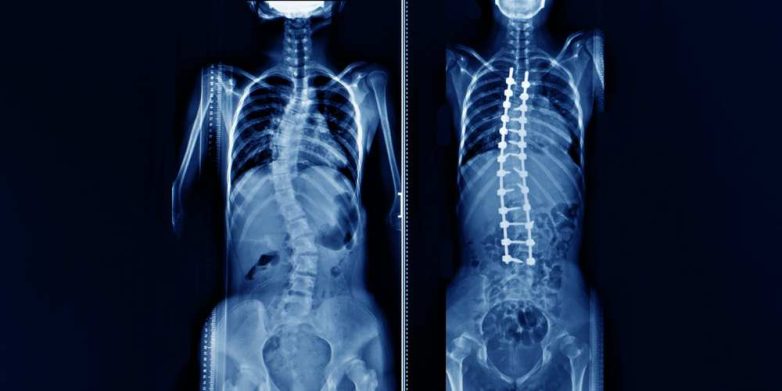

Сколиоз позвоночника. Слева — с ярко выраженным искривлением, справа — после коррекции.

Подросткам и молодым людям, которые перестали расти, проводят спондилодез. Во время такой операции позвоночник выпрямляется с помощью металлических стержней, винтов, крючков или проволоки, а также фрагментов кости, взятых из другой части тела, часто из бедра.